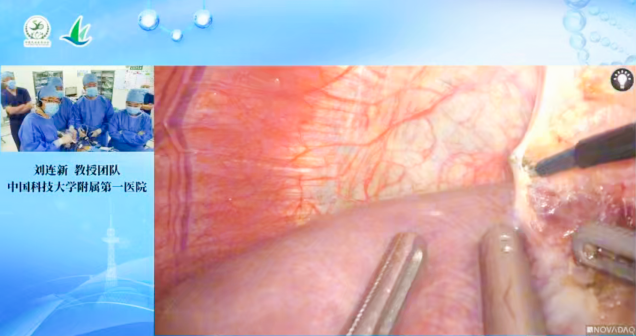

“手术直播”中,中国科学技术大学附属第一医院刘连新教授团队、哈医大肿瘤医院邰升教授团队的手术直播直观展现“精准肝胆胰手术视界”。刘连新教授团队的手术从切口选择到血管处理尽显专业功底,专家实时拆解术中出血控制、术后肝功能保护等硬核技巧;邰升教授团队则结合本地患者特点,展示“保证切除范围同时保留更多肝组织”的个体化策略,极具临床借鉴意义。

刘连新教授团队手术直播 邰升教授团队手术直播